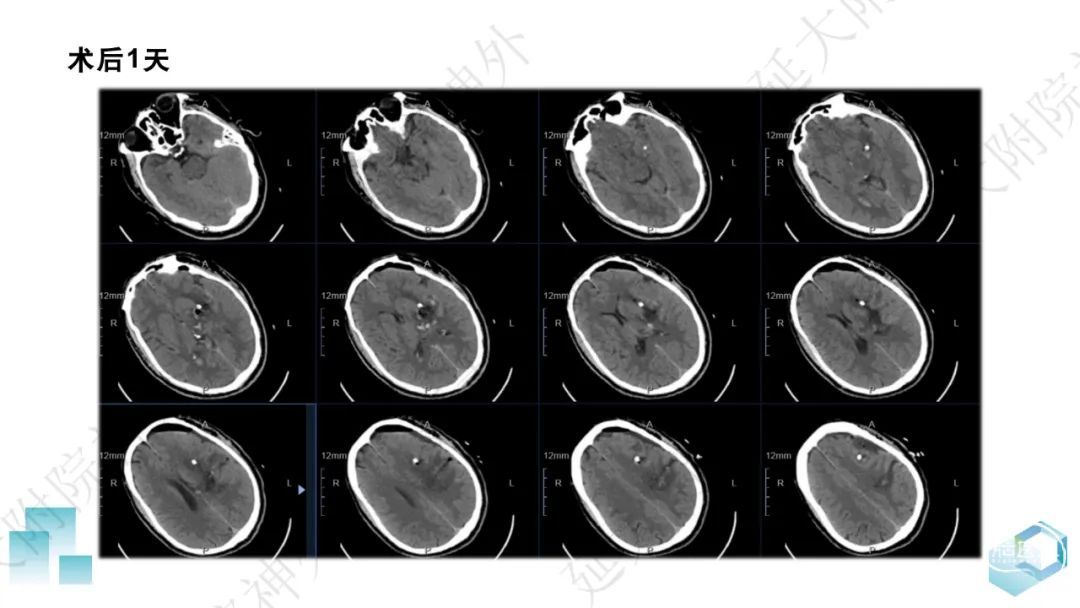

今天为大家分享的是《监测有道丨颅脑创伤-神经重症周刊》第332期,由延安大学附属医院神经外科贾云峰主任医师带来的:左侧基底节区出血破入脑室一例神经内镜下血肿清除术,欢迎阅读、分享。